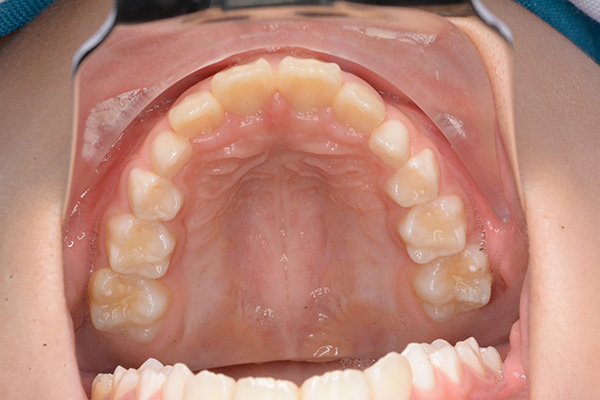

動的治療終了時

FP・IOP

批評・予后 本来であれば永久歯歯列完成後に本格矯正治療を行って良い症例だが、患者さん(保護者)の強い希望から早期治療にて改善を行った症例である。バイオネーターを夜間就寝中に使用して咬合誘導を行った結果、前歯の前突感は解消され比較的緊密な咬合は得られたように思う。